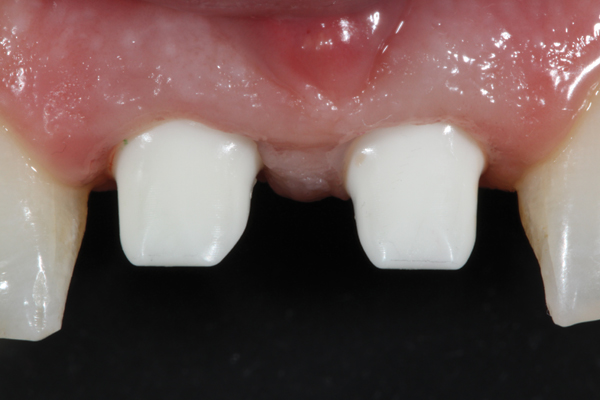

Fig 1. The “emergence profile” is the area of the abutment extending from the head of the implant to the free gingival margin.

Figure 1

Following the successful integration of implants in the esthetic zone and creation of satisfactory hard- and soft-tissue volume, the restoring clinician is responsible for managing and shaping the definitive soft-tissue architecture. In the esthetic zone, this is a process generally achieved through the use of an implant-retained provisional restoration. The restoring clinician and technician should be intimately familiar with esthetic principles of tooth size, shape, and position. However, the subgingival area of the provisional restoration is also vitally critical. This area, known as the “emergence profile” (Figure 1), plays a significant role in the creation and maintenance of a satisfactory gingival architecture and will ultimately determine the final architecture of the peri-implant soft tissue.